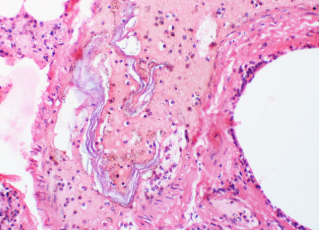

Dr Gregory Collins lecture “Recognition and Management of Amniotic Fluid Embolism” is a comprehensive review of signs/symptoms, causes and treatments of Amniotic Fluid Embolisms. This course is valued at 1 Class A CE.

Course #081 Amniotic Fluid Embolus Diagnosis and Treatment